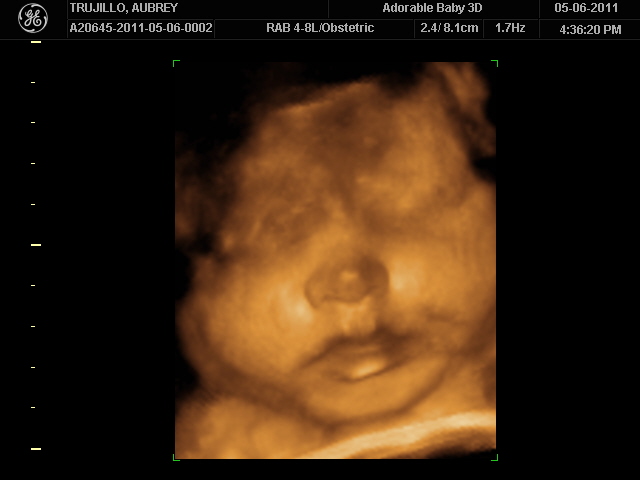

20 weeks - profile20 weeks - Profile again20 weeks - Right foot!20 weeks - sucking thumb!!!!20 weeks - hand near face20 weeks - flexing his bony arms!20 weeks - hiding from mommy and daddy!20 weeks - it's a boy!33 weeks - 3D!33 weeks - 3D!33 weeks - 3D!